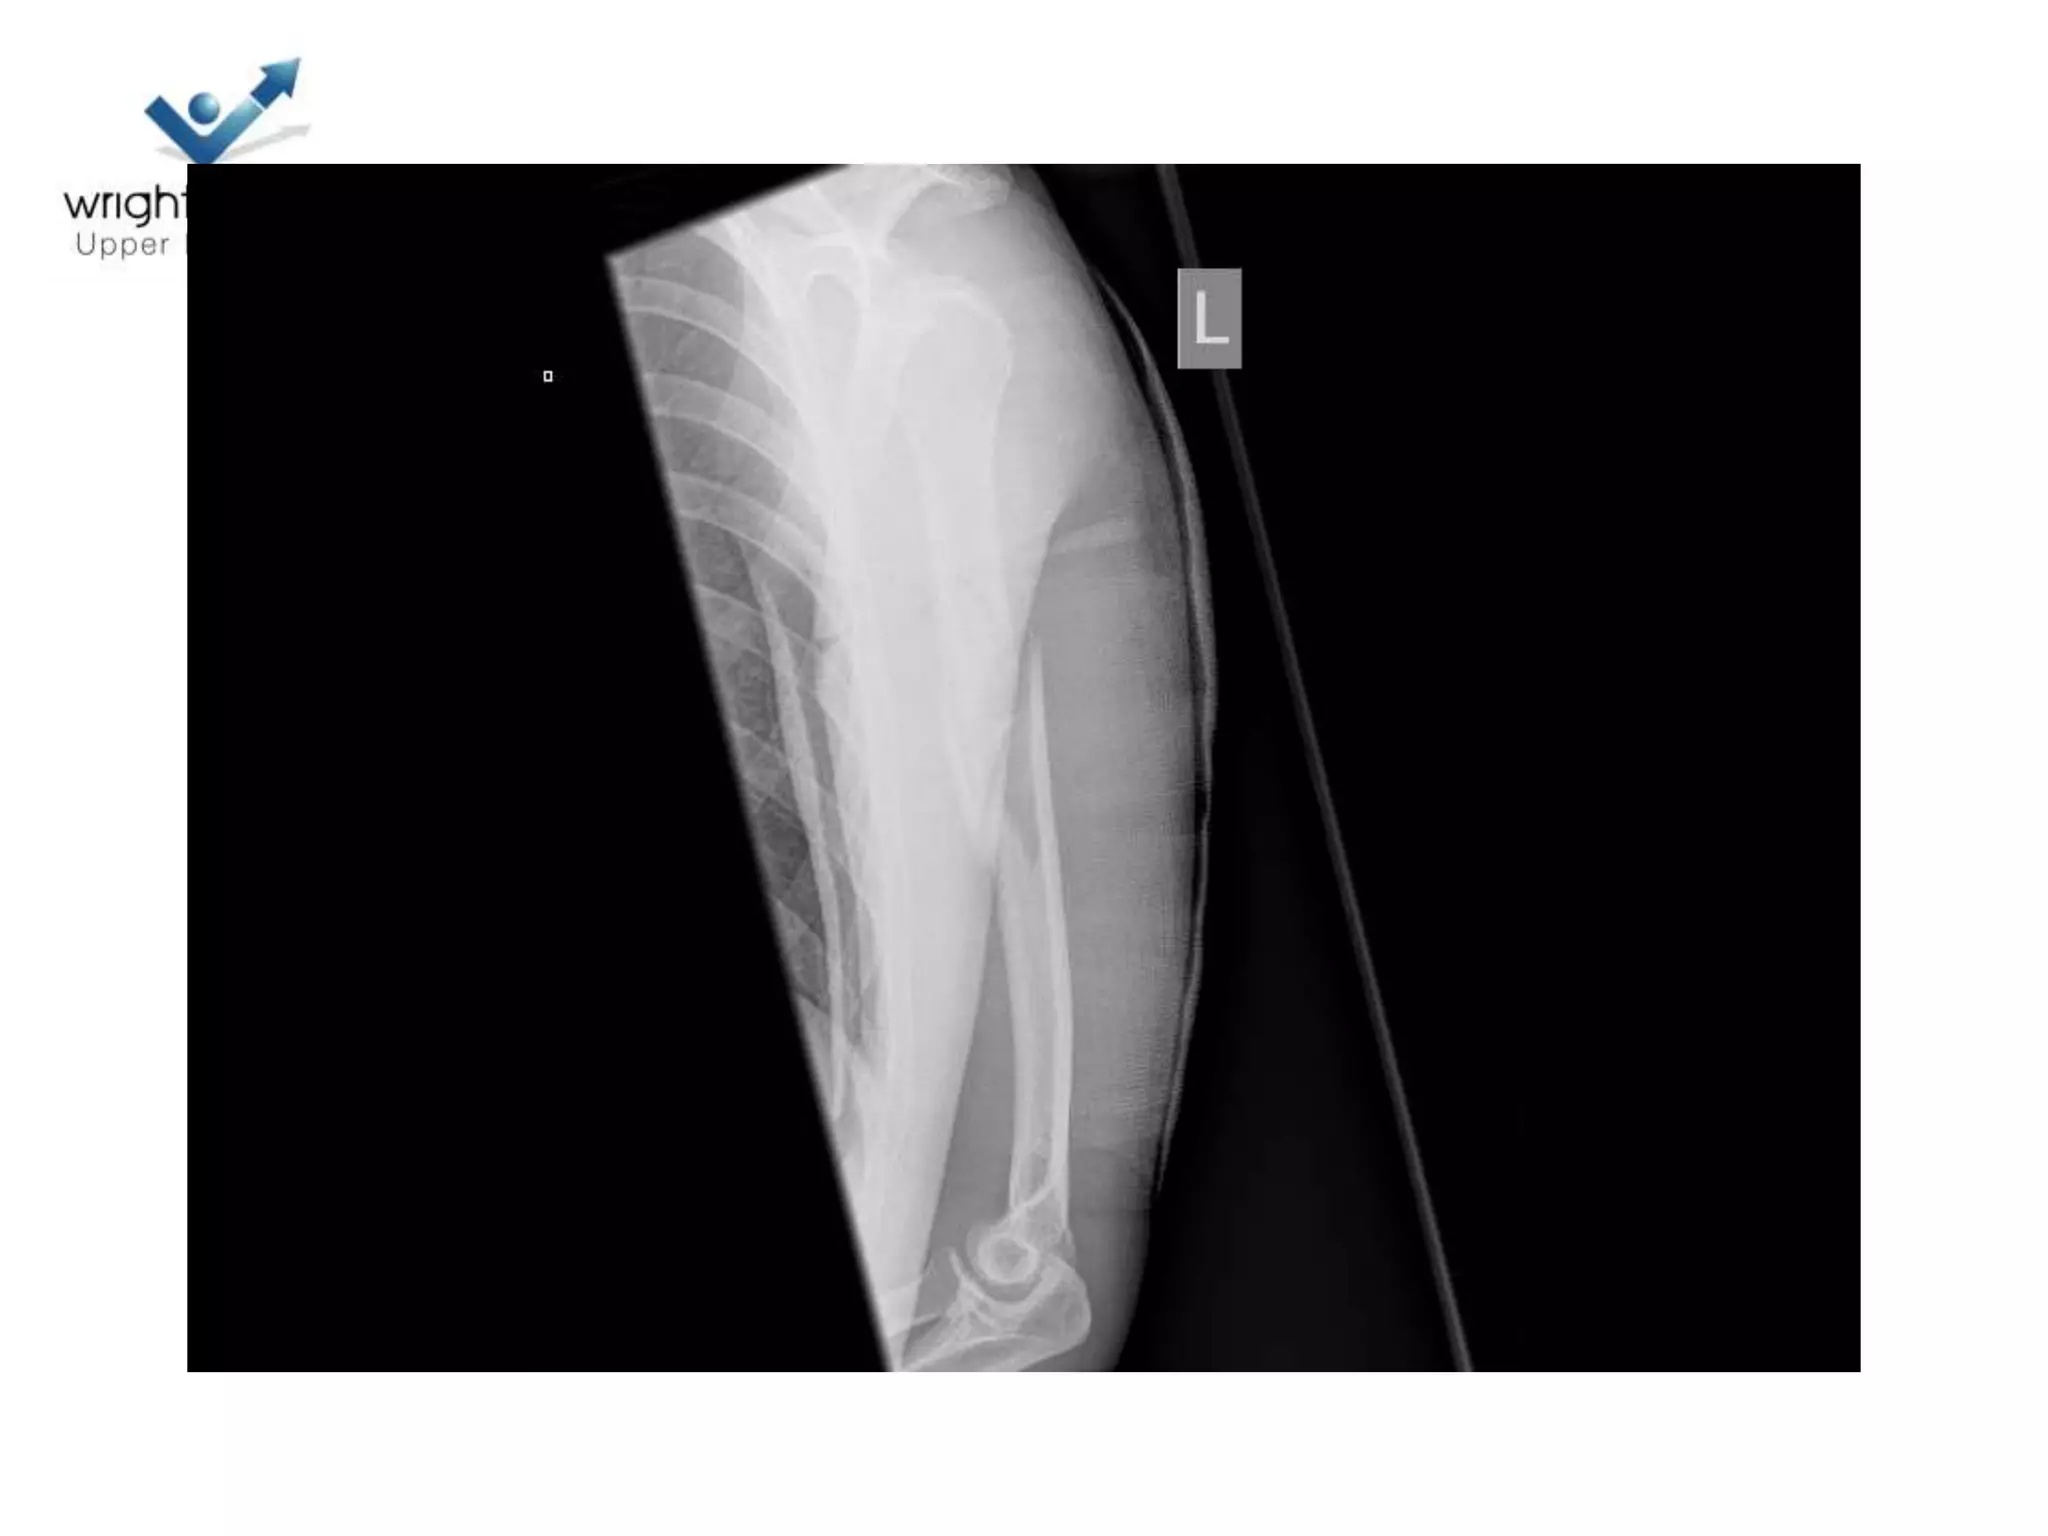

17 Polytrauma

Let’s put it all together

Indications to operate

• Prevent Non union

– Shaft pulled medially